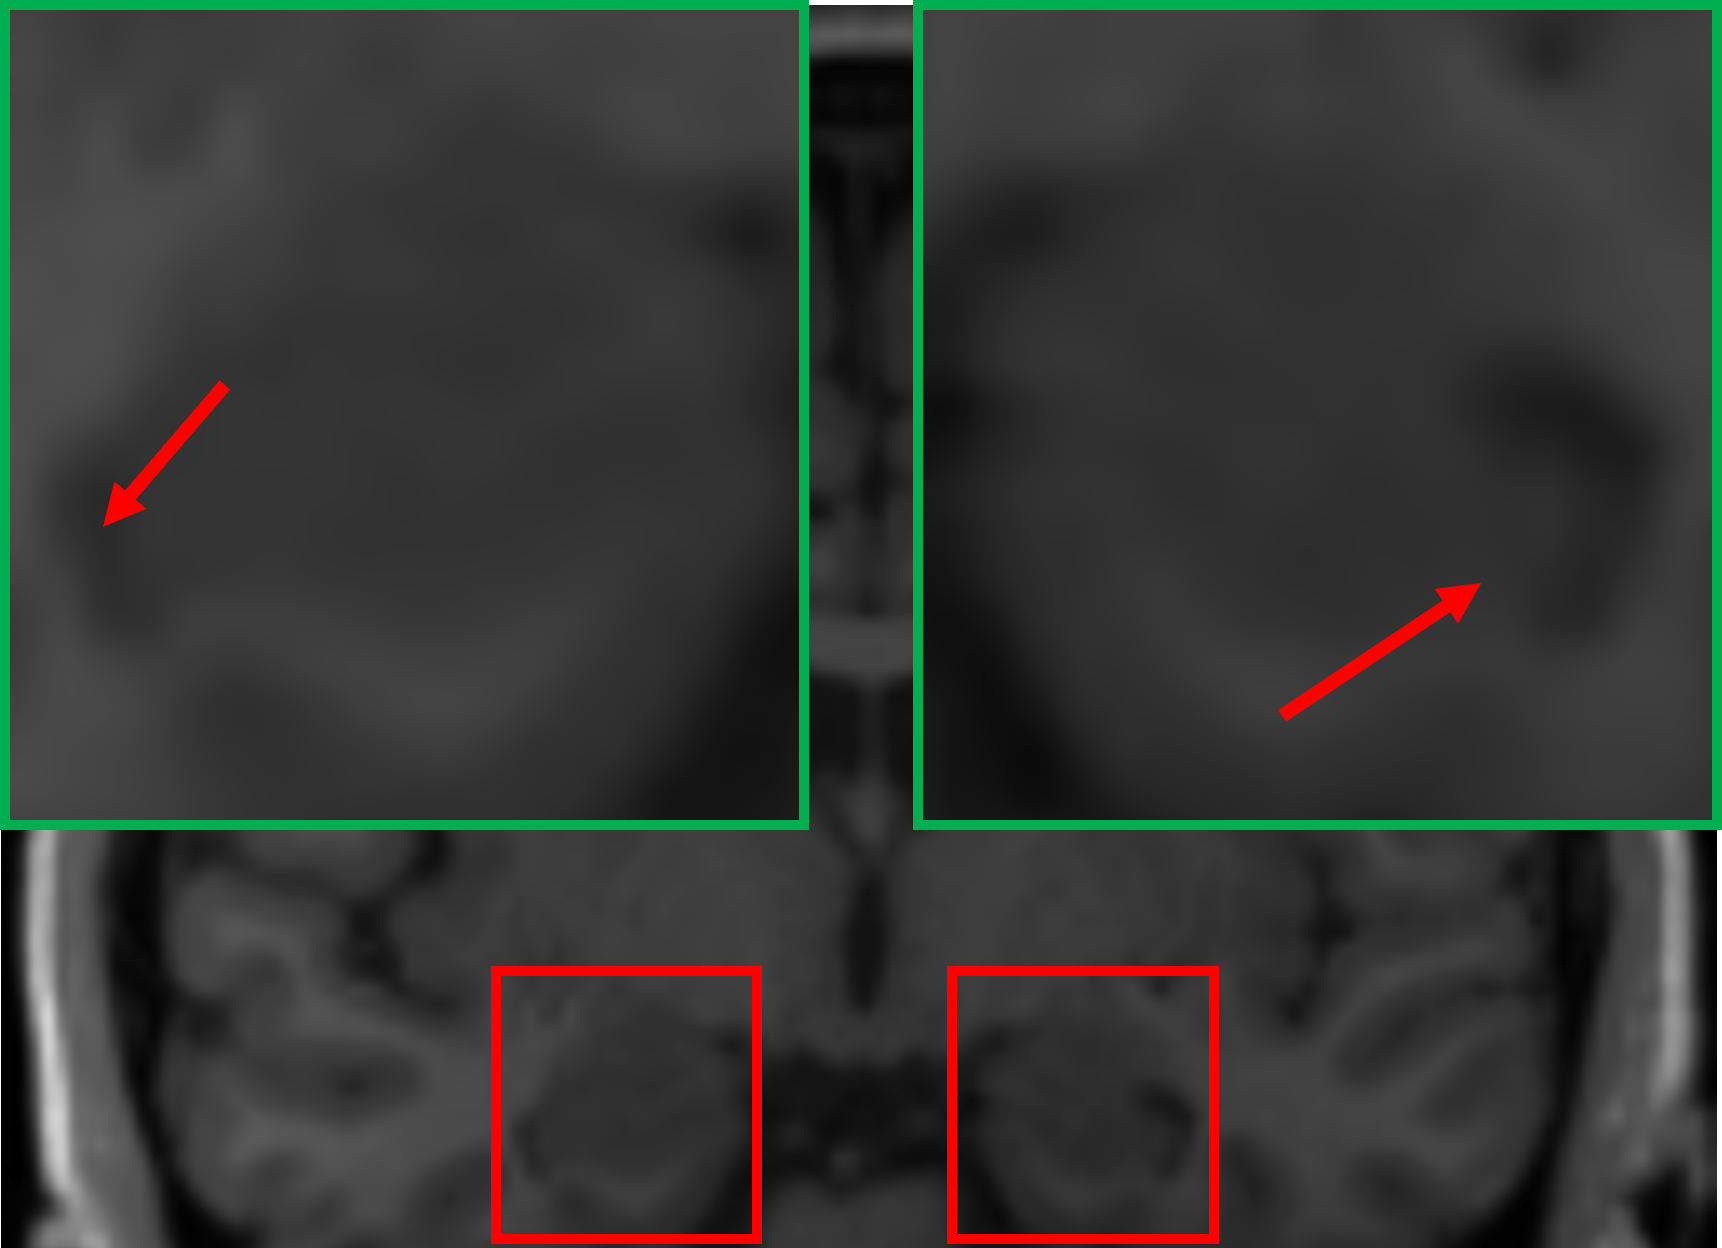

TABLE VI: Clinical evaluation for seizure case

Real 1.5T MRI Real 3T MRI 3T-like SR MRI (1.5T to 3T)

In one case, for a patient with partial seizures and secondary generalization, an initial diagnosis using 1.5T MRI revealed a mild volume loss in the left hippocampus, further imaging with 3T MRI was recommended to confirm the diagnosis. As shown in Table VI, the green boxes highlight the hippocampus region, while the red arrows point to areas indicative of water content within the hippocampus. In the 1.5T MRI, the patient’s hippocampal asymmetry can be appreciated with large sulci with water content on the left side (right sub-image), suggesting mesial temporal lobe atrophy. This observation was confirmed more clearly in the subsequent 3T MRI, which provided a sharper depiction of the sulcal enlargement in the same region, reinforcing the diagnosis of mesial temporal disease. Notably, by applying our student model to perform SR on the 1.5T MRI, the resulting 3T-like MRI closely resembled the actual 3T MRI. The obtained image not only improved the clarity of the hippocampal structure but also effectively captured the increased water content in the left hippocampus, closely matching the pathology observed in the 3T MRI, which underscores the clinical potential of our super-resolution framework in enhancing diagnostic capabilities. By applying our student model to super-resolve the 1.5T MRI to a 3T-like resolution, the resulting image closely resembled the actual 3T MRI. The 1.5T-based SR image not only improved the clarity of the hippocampal structure but also effectively captured the increased water content in the left hippocampus, closely matching the pathology observed in the 3T MRI.